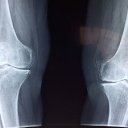

Artróza kolenního kloubu a možnosti její léčby

Gonartróza je artróza, která postihla kolenní kloub. Hlásí se bolestmi kolenního kloubu při pohybu a v pokročilejším stádiu se přidávají i bolesti klidové. Často pozorujeme omezení pohyblivosti kloubu, otok kolena nebo mírně…